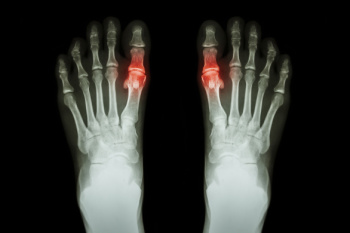

Gout is a form of inflammatory arthritis caused by high levels of uric acid in the blood, which leads to the formation of sharp crystals in the joints. Gout commonly affects the big toe and foot, causing intense pain, swelling, redness, and warmth. Symptoms often appear suddenly and can make walking difficult. Causes include the body producing too much uric acid or not removing enough through normal processes. Risk factors include genetic predisposition, excess body weight, high blood pressure, and diabetes. Diet and lifestyle choices may also contribute to flare-ups. A podiatrist can diagnose gout, recommend treatments to reduce pain and inflammation, and provide guidance on managing symptoms and preventing future attacks. Gout can be extremely painful and may cause difficulty in completing daily activities. If you have sudden foot pain or swelling, it is suggested that you promptly consult a podiatrist who can help you to manage this painful condition.

Gout is a form of arthritis that is characterized by sudden, severe attacks of pain, redness, and tenderness in the joints. The condition usually affects the joint at the base of the big toe. A gout attack can occur at any random time, such as the middle of the night while you are asleep.

- Intense Joint Pain - Usually around the large joint of your big toe, and it most severe within the first four to twelve hours

- Inflammation and Redness -Affected joints may become swollen, tender, warm and red